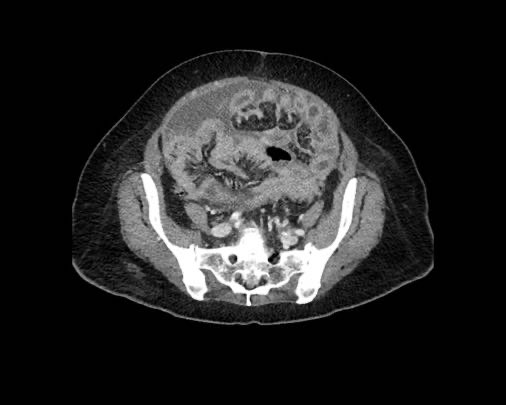

Cuộn xem ảnh CT

Ca lâm sàng 1

Cuộn qua các lát cắt.

Bạn có thể phát hiện tất cả các tổn thương cấy ghép phúc mạc không?

Bệnh nhân này đã được phẫu thuật và toàn bộ phúc mạc được ghi nhận phủ kín bởi các tổn thương u dạng kê.